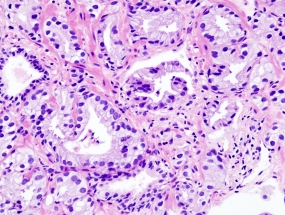

Bei Lutetium-177 PSMA-617 handelt es sich um einen mit radioaktivem Lutetium-177 gekoppelten Liganden, der an das Prostata-spezifische Membranantigen, kurz PSMA, passgenau andocken kann. Die Mehrzahl aller Prostatakrebszellen trägt das Glykoprotein PSMA auf ihrer Zellmembran, im übrigen Körper kommt es dagegen kaum vor. Die Krebszellen nehmen den Wirkstoff ins Zellinnere auf, so dass er sich in den Tumoren anreichert und von innen heraus seine tödliche Strahlendosis abgibt. Das macht die Wirkung der Therapie besonders präzise und zielgenau.